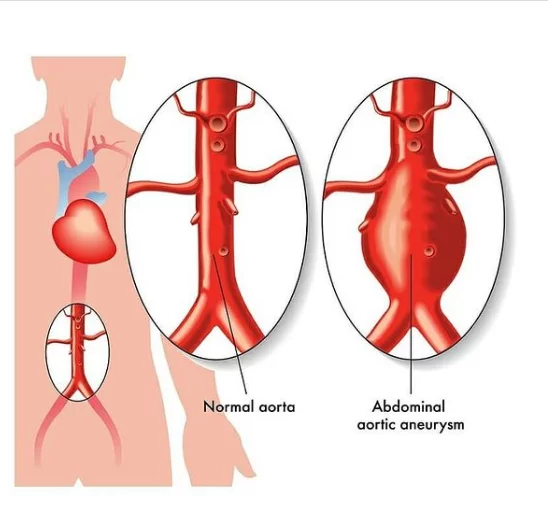

این بیماران با احساس ضربانات مداوم در شکم و درد و گاهاً بدون علامت در معرض خطر پارگی رگ اصلی بدن به نام آئورت ومرگ ناگهانی هستند .دیروز در کمتر از یکساعت بدون جراحی ، استنت هایی که پوشش دیواره ای دارند را مثل لوله داخل ناحیه آنوریسم/یا گشاد شده، تعبیه کردیم و آئورت به سایز نرمال برگشت.

درمان آنوریسم آئورت شکمی1